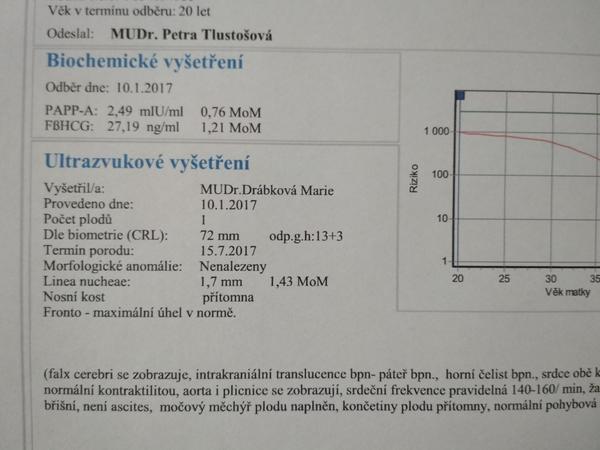

@seveneye mne ty hodnoty nic neříkají, posílám scan😉

@jednaholkaa já tam právě žádnou tu hodnotu volného Hcg nemám, jen to MoM

Ono se to zpřeházelo. Jsou tam vidět datumy.. 🙄

@jednaholkaa Tady jsem schválně našla ty výsledky z předchozích těhotenství 🙂 Obě to jsou holky 🙂 A hodnoty nízké 🙂 Teď zatím hodnoty nevím, na screening jdu ve čtvrtek :D